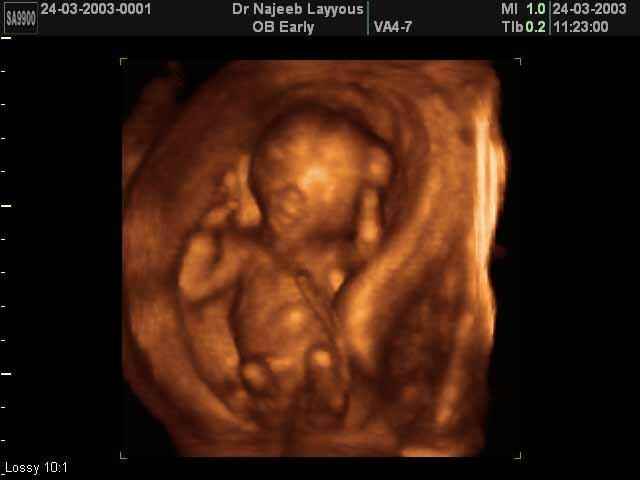

3D First Trimester Ultrasound Scan Photos ( Early Pregnancy Ultrasound Photos ) | Dr N Layyous

3D First Trimester Ultrasound Scan Photos